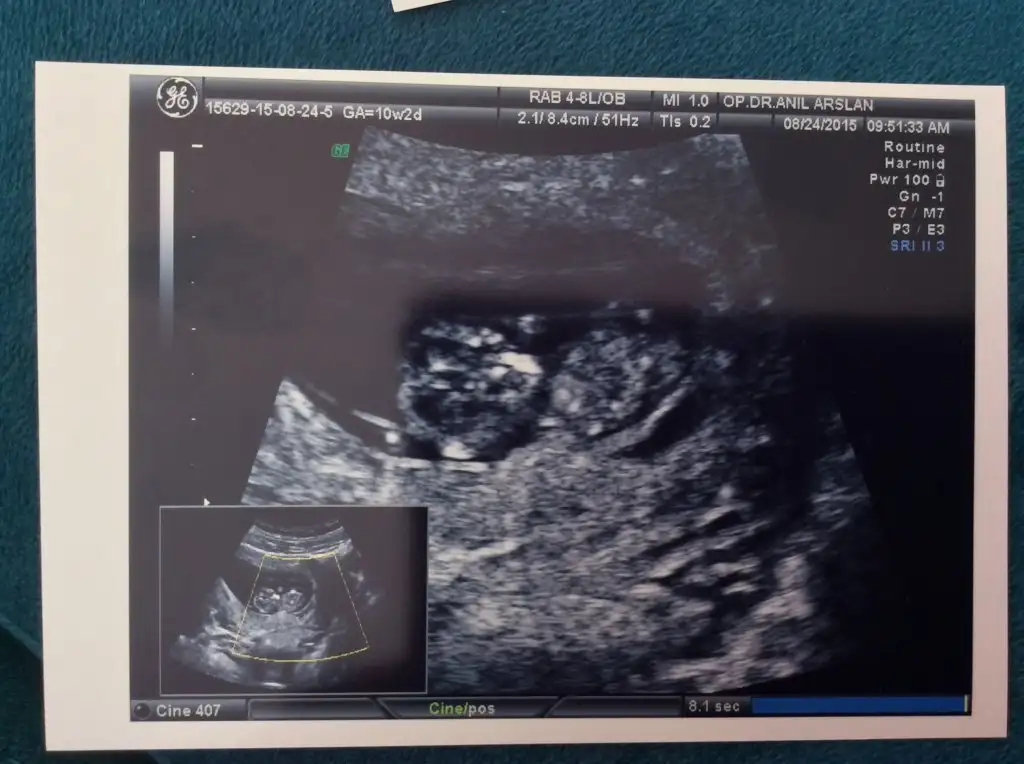

Herkese merhabaaaalar :) çok mutluyum randevumuz vardı bugün doktorumla :) bebişim tam 10 hafta 2 günlük :) adet tarihime göre de ultrasona göre de :) hiç bir problemimiz yok şu an Allah'a şükür... Allah'ım kimseye de dert vermesin.

3,5 cm olmuşuzkalbimiz kuş gibi atıyordu

9 gün sonra ikili teste gidicez inşallah